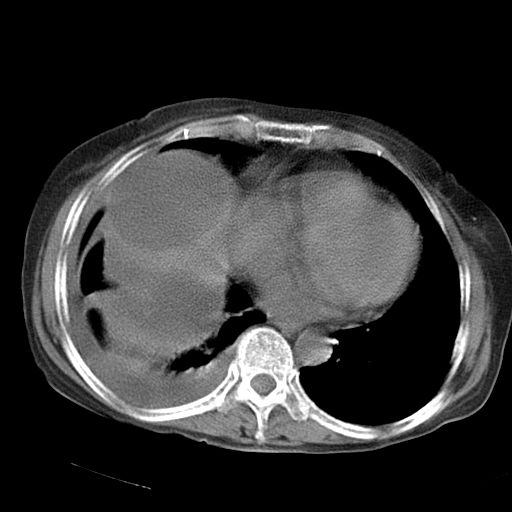

以下是引用dyqct在2006-12-7 21:08:00的发言:[br]考虑:1、肝内外胆管多发性结石伴肝左叶外侧段肝萎缩;[br] 2、右膈下多发脓肿;[br] 3、右侧少量胸腔积液、斜裂积液;[br] 4、左肾囊肿。

以下是引用拾荒者在2006-12-7 21:44:00的发言:[br]肝内外胆管多发结石,右膈下多发脓肿,右胸膜腔及叶间裂积液,左肾囊肿。[br] [br]